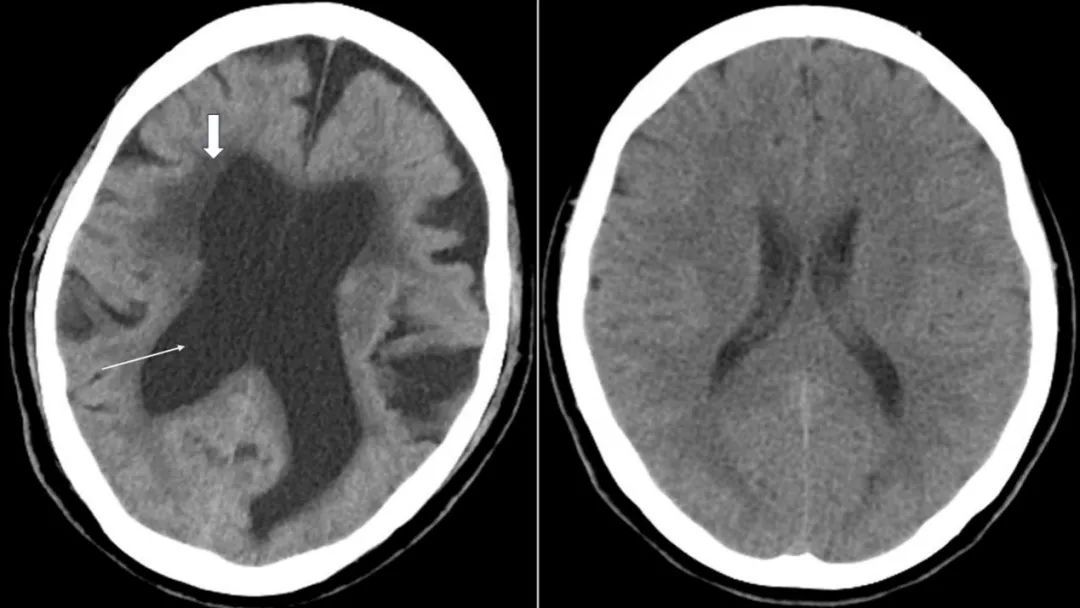

上图为正压性脑积水患者CT表现,可见脑室明显扩大(细箭头为脑室),脑室周围脑组织可见显著水肿(粗箭头为脑室旁水肿);右图为正常成人头部CT,脑室无扩张。

医生在门诊中遇到此类患者时,首先会详细询问症状开始时间、进展情况以及可能的诱因等。针对脑积水,头部CT或磁共振检查尤为重要,可以直观观察脑室的大小和形态,以及周围脑组织受压情况,严重者可见脑室旁组织水肿,医生可根据影像学表现评估患者脑积水严重程度。治疗前还需要评估患者的运动功能,并进行神经心理测试(包括认知功能、记忆力、注意力、执行功能等)。